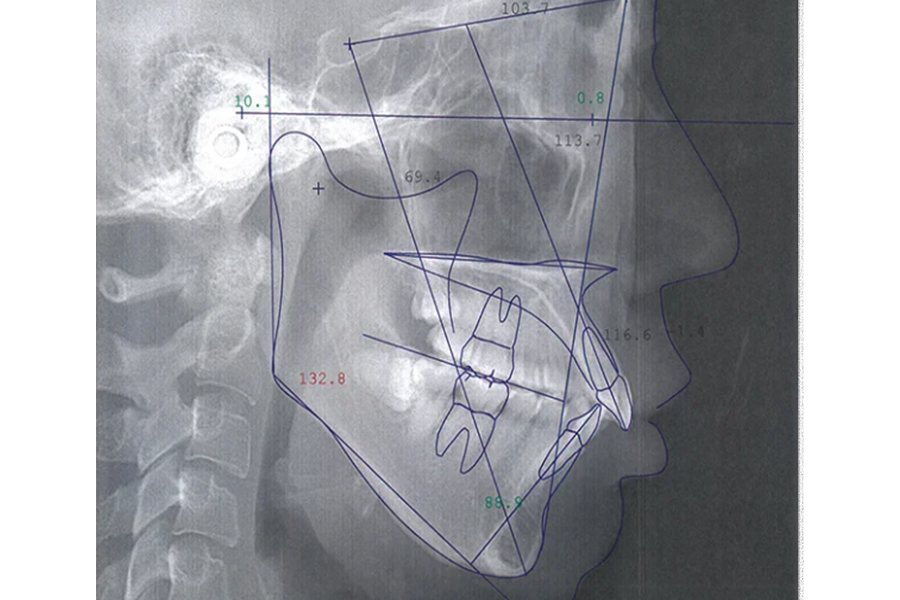

- レントゲン撮影

患者様のお口の詳しい情報を収集し、分析・診断を行います。

| 治療名 | 上唇小帯切除術、 アライナー矯正治療 |

| 患者様情報 | 10代 女性 |

| 担当医 | 高橋 隼平 先生 |

| 費用 | 800,000円 (税込) |

| 主訴 | 見た目が気になっている。上の前歯は歯ブラシが当たると少し痛い。 |

| 治療期間 | 約1年6ヶ月 (約2~3ヶ月に 1回ペース) |

| 治療内容 | 見た目が気になり、上の前歯は歯ブラシが当たると少し痛いとのことで来院されました。 上唇小帯については、上唇小帯切除術し、傷口が治癒した後は、インビザラインにて矯正治療を行いました。 |

| 治療のリスク | 矯正治療後、保定装置をしっかり使わないと後戻りする可能性があります。 |